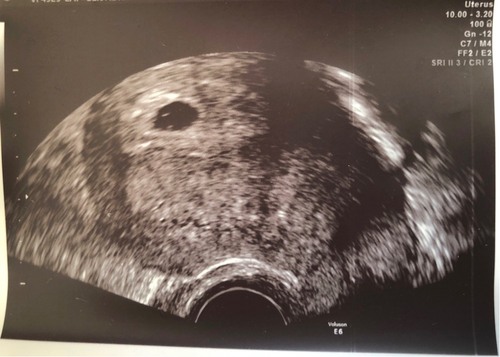

Ich bin 34 und bin nach einer Fehlgeburt in der 6. Woche nach drei Zyklen wieder schwanger geworden. Ich habe dieses Mal ein anderes Gefühl und hoffe, dass es sich richtig festgebissen hat. :) Am 1.5. wäre Termin, am Donnerstag habe ich den ersten Frauenarzttermin zu Beginn der 7. Woche (6+0)...

Mein ET ist der 01. Mai und ich sollte jetzt bei 6+5 sein.

Bin das erste mal schwanger in der 5SSW plus 4 Tage :).